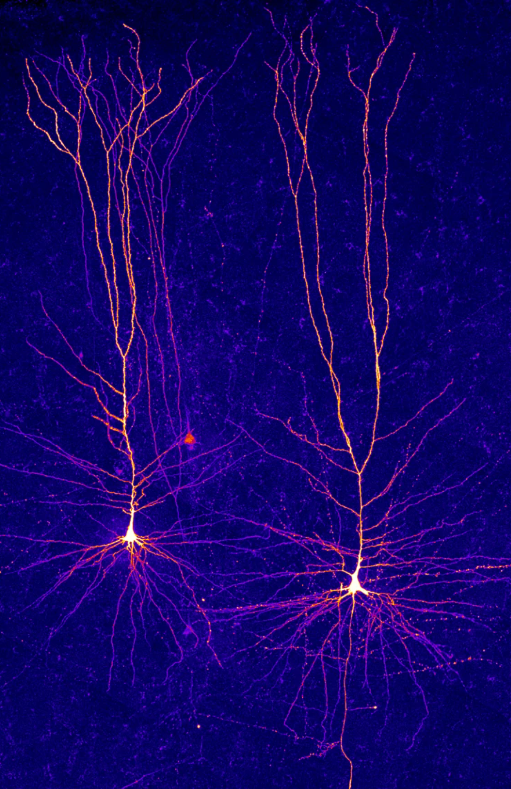

Neurons in layer 2/3 of the human neocortex.

Credit: Humboldt University of Berlin